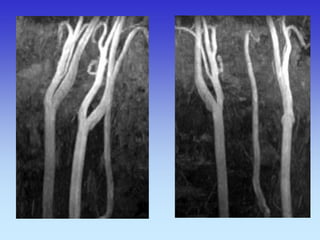

METODE PRIKAZA KRVNIH ŽILA

•UZ-DOPPLER

•DSA

•CTA

•MRA

B-mod i obojeni Doppler karotidne arterije